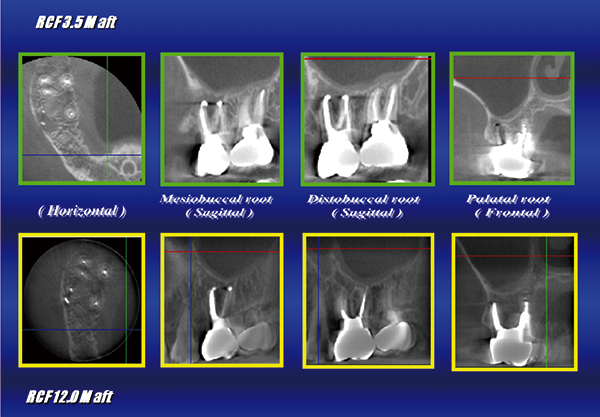

The following year, 2006, I invented a new root canal cleaning procedure,

"EndoWave All-Ranges version," and I felt that I had perfected my own procedure of cleaning root canals. (Figures 4 and 5)」

For this reason, in a patient with a large amount of dissolved bone around the root(Fig. 6),